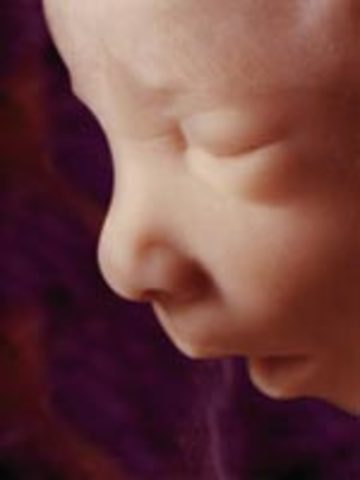

The fetus starts to move. the face begin to look like a baby face.

• Week Thirteen: Baby flexes and kicks

Week Thirteen: Baby flexes and kicks

The movements can be measured. the chin and nose are well defined.